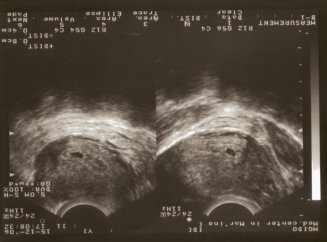

Határozzuk meg a 100% -a terhes nők, a második héten még mindig elég nehéz, mert a HCG szintje még mindig nagyon kicsi, és miután egy gyermek mutathat csak egy teszt, amelynek az érzékenysége 10 egység. Egy megbízható módon megállapítani a terhesség ultrahang. A tanulmány nem csak megerősítette a jelenlétét a gyermek, hanem azt is mutatják, hogy a embrió látszik: 2 hét - még túl kevés idő, de ebben a pillanatban már kezd érezhetővé válni a magzati élet.